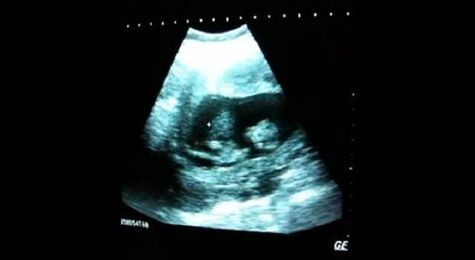

يعلق طفل صغير لدى رؤيته أخته الجنين، وهي تقفز داخل رحم أمه، كما يظهر جلياً على شاشة الموجات فوق الصوتية، أثناء كشف طبي تجريه الأم الحامل في عيادة أحد الأطباء.

في هذا الفيديو المنشور على موقع "يوتيوب" قبل أكثر من ست سنوات، يمكنكم رؤية القفزات التي يقوم بها الجنين داخل رحم أمه وكأنه يلعب مستمتعاً على سرير مطاطي. حيث حظي بأكثر من 5 ملايين مشاهدة حتى اليوم.

الأم شيرين غايل-سلاتر، والتي أعادت نشر الفيديو قبل أسبوعين، مما تسبب باشتعاله سريعاً على مواقع التواصل الاجتماعي، أجابت على تساؤل المتابعين عندما سألوها عن عمر جنينها يوم التقطت له هذا الفيديو وكتبت: "أعتقد أنني كنت بين الأسبوع 8-12 من أسابيع الحمل، لأنني لم أكن أشعر بتحركاتها. ولم أصدق ما رأيته يومها، كان فرحاً مطلقاً".